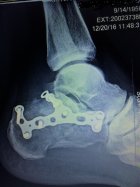

Well, they've finally got room in the shop for me. My Chick is dropping me off in the morning, and the mechanic is taking all this hardware out. If everything goes well, I'll wake up with both feet and a couple weeks worth of good dope. If things go bad, I'll wake up with Jesus.